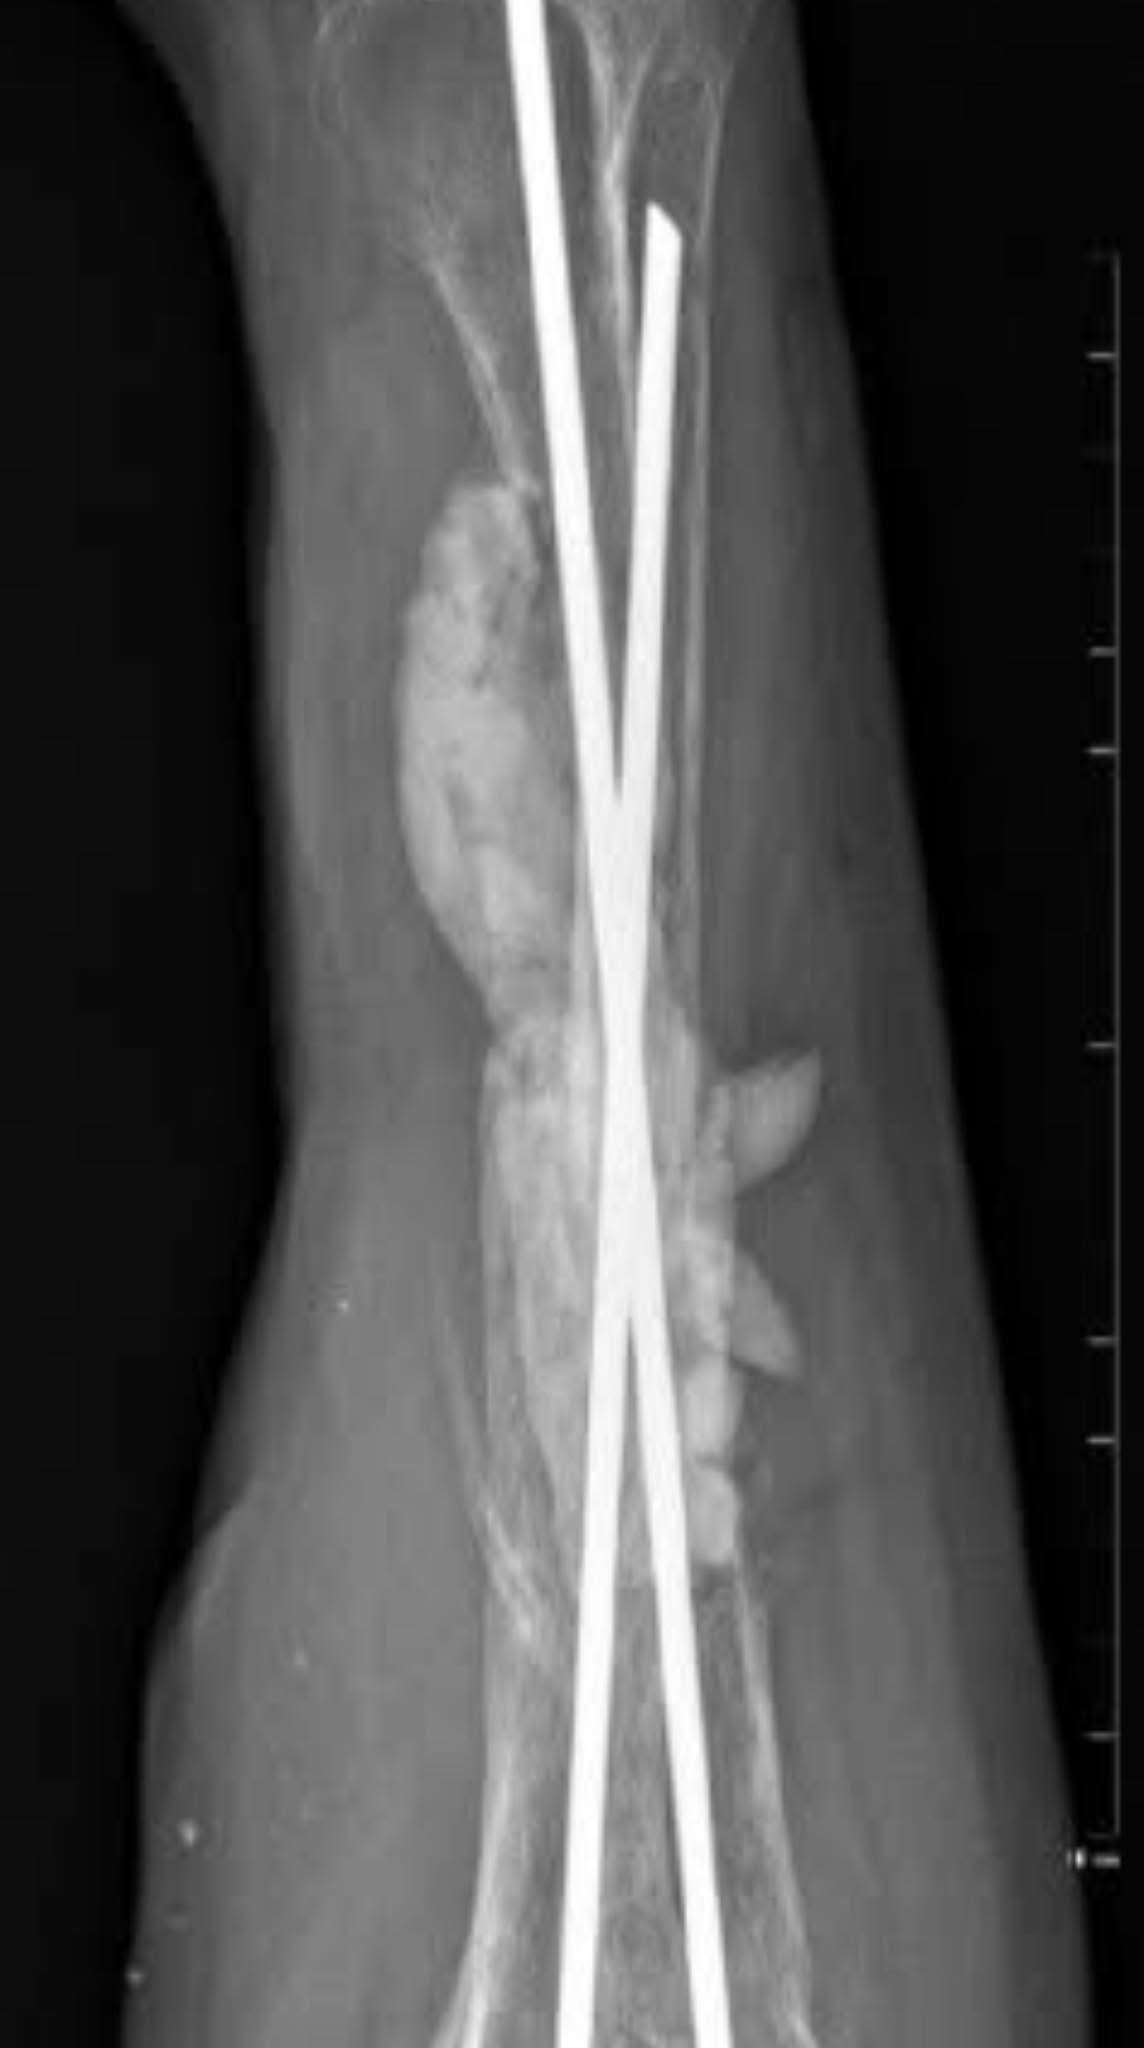

У травні 2023 року пацієнт С. зазнав мінно-вибухової травми, наслідком якої став відкритий вогнепальний перелом обох кісток правого передпліччя з значним дефектом кісток і м’яких тканин.

• Відкрите вправлення,

• Видалення нежиттєздатних уламків променевої кістки,

• Остеосинтез інтрамедулярними стержнями,

• Заміщення дефекту цементним спейсером із антибіотиками.

На цьому етапі дефект променевої кістки складав 12 см.